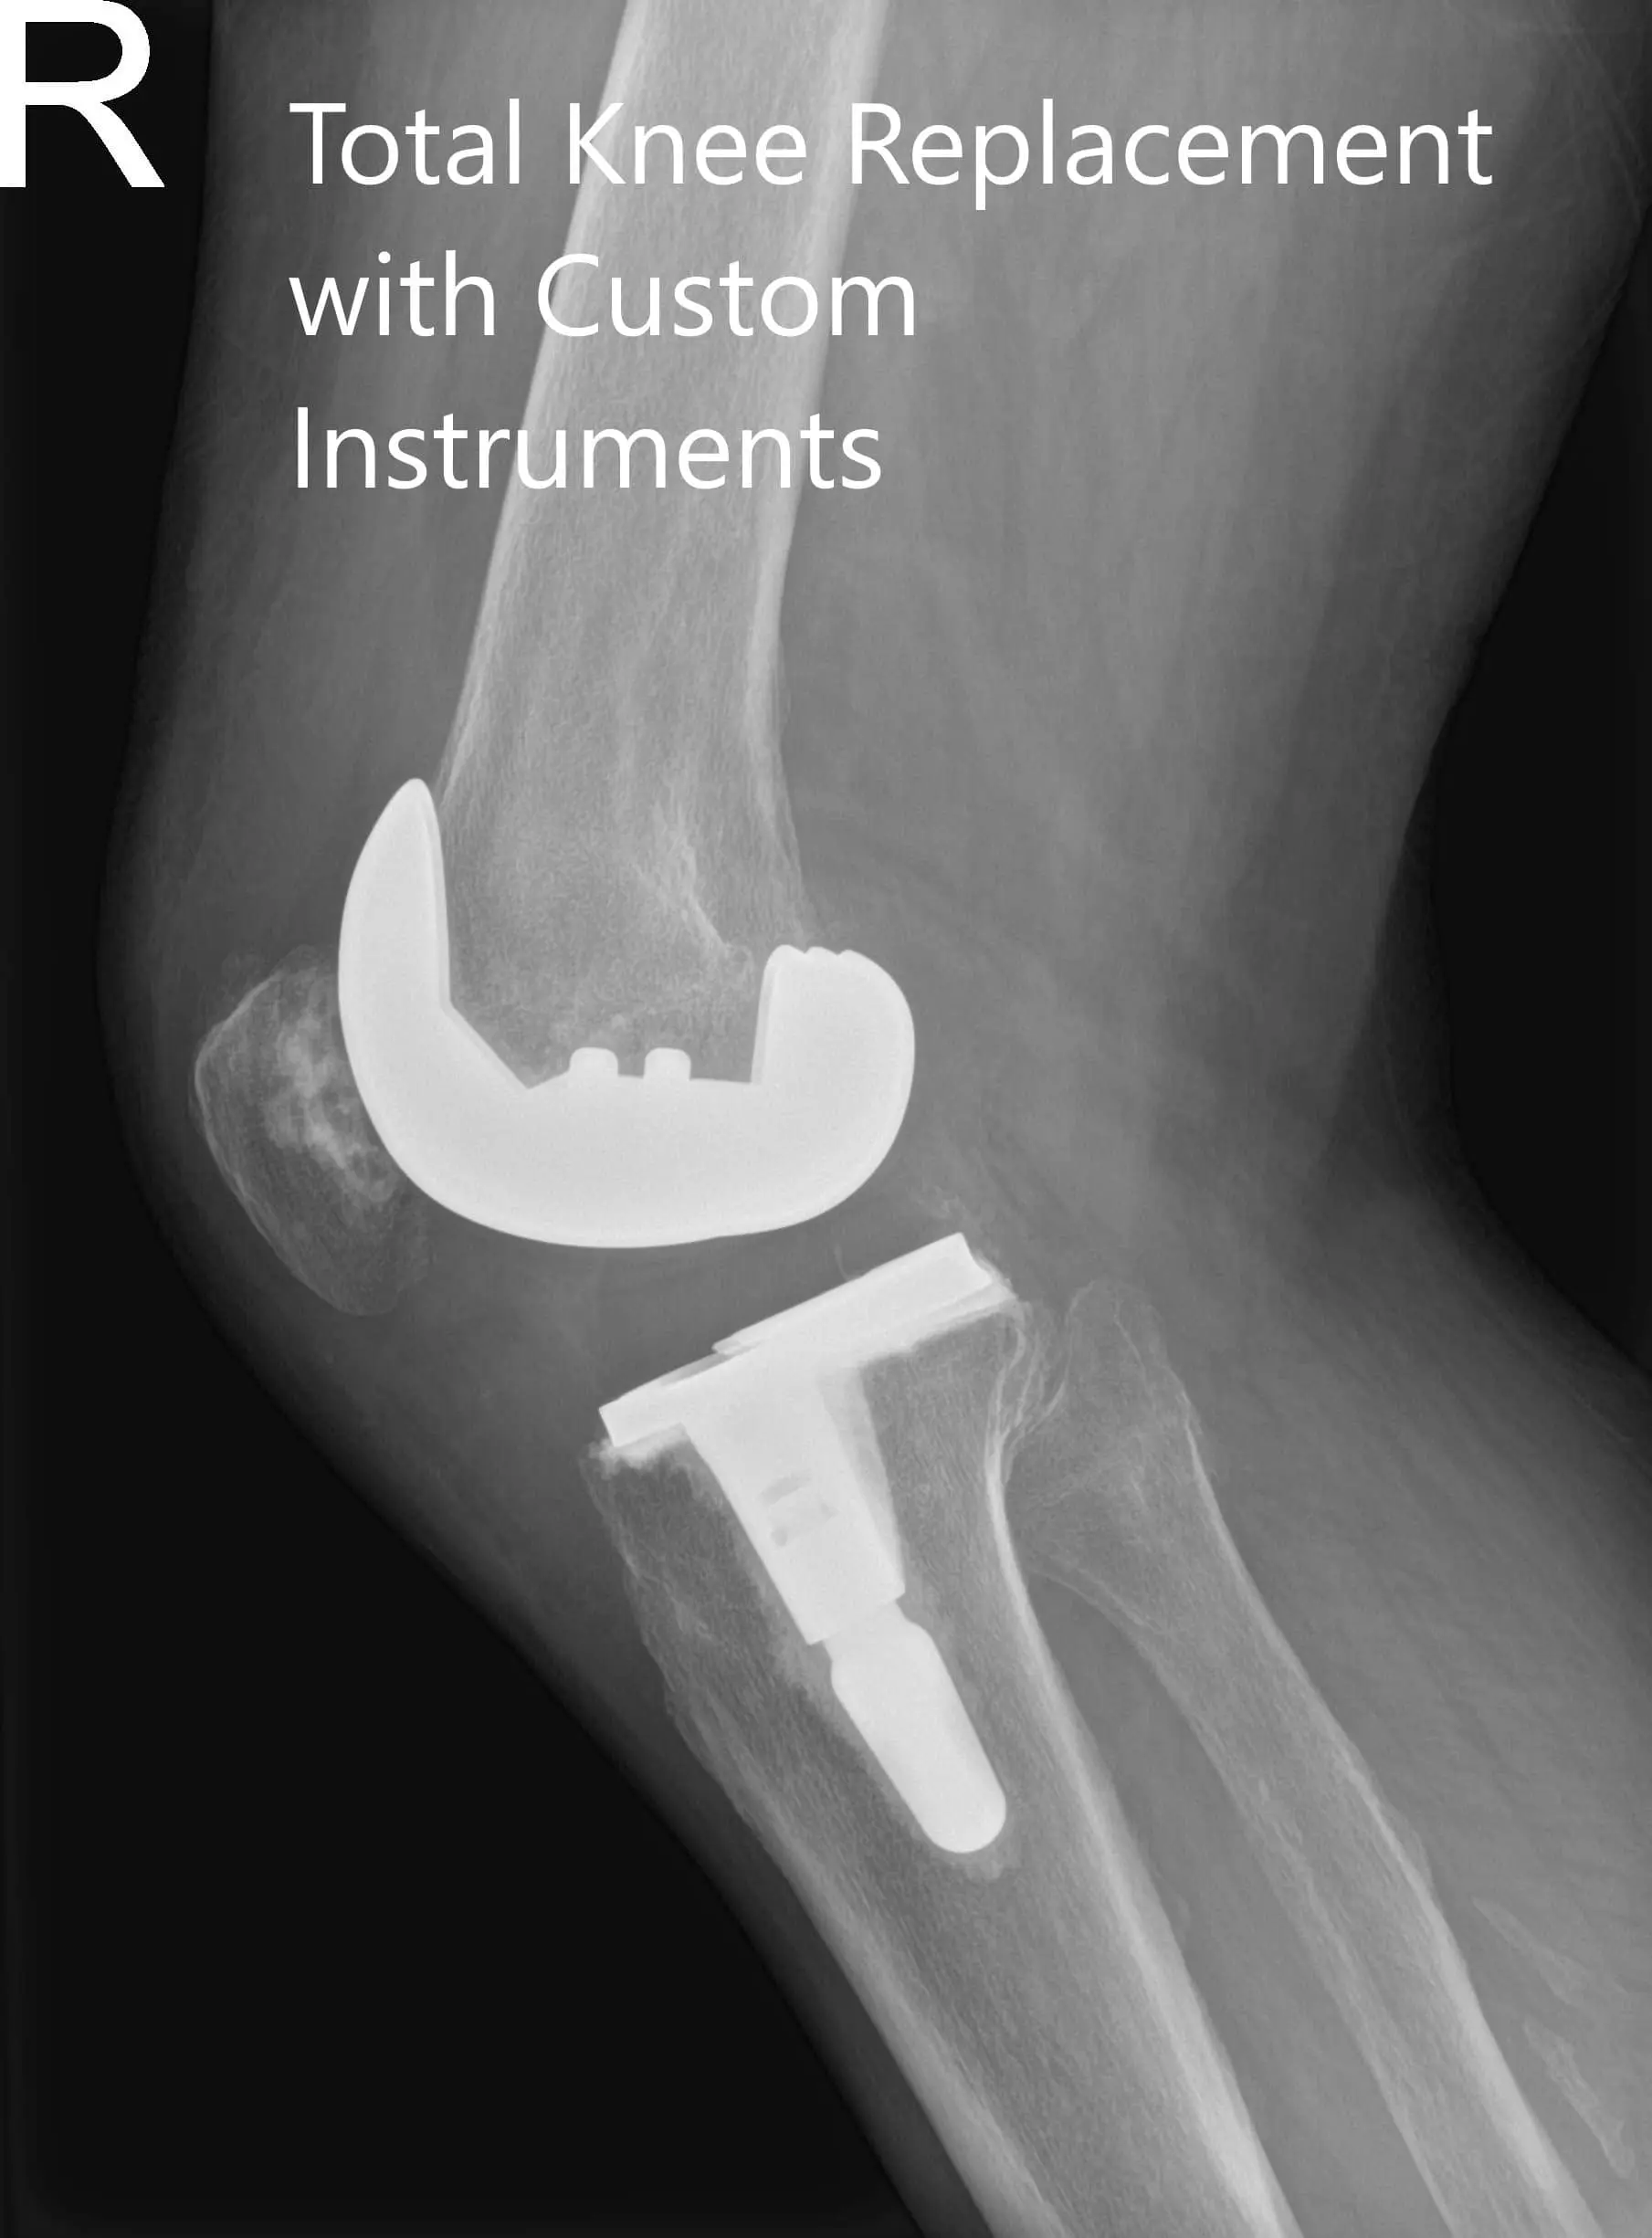

ostoperative X-ray of the right knee in anteroposterior and lateral views

Postoperative X-ray of the right knee in anteroposterior and lateral views.